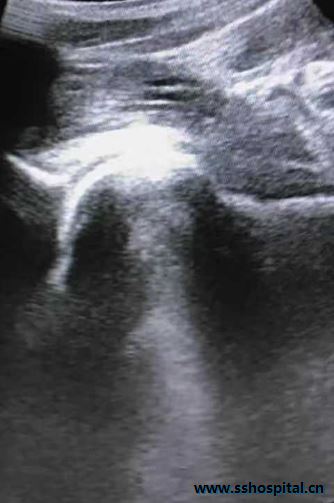

MR提示炎症 超声引导下髋关节腔三氧注射治疗

吕生因曾经过近3个月的药物治疗病情并未好转,对药物治疗失去了信心。结合吕生情况,中医科采用超声引导下髋关节三氧注射治疗。经过2次治疗后吕生关节疼痛完全消失,活动恢复正常。